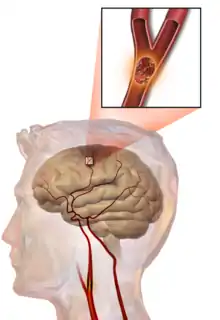

Embolic stroke

An embolic stroke refers to an arterial embolism (a blockage of an artery) by an embolus, a traveling particle or debris in the arterial bloodstream originating from elsewhere. An embolus is most frequently a thrombus, but it can also be a number of other substances including fat (e.g., from bone marrow in a broken bone), air, cancer cells or clumps of bacteria (usually from infectious endocarditis).[45]

Because an embolus arises from elsewhere, local therapy solves the problem only temporarily. Thus, the source of the embolus must be identified. Because the embolic blockage is sudden in onset, symptoms usually are maximal at the start. Also, symptoms may be transient as the embolus is partially resorbed and moves to a different location or dissipates altogether.

Emboli most commonly arise from the heart (especially in atrial fibrillation) but may originate from elsewhere in the arterial tree. In paradoxical embolism, a deep vein thrombosis embolizes through an atrial or ventricular septal defect in the heart into the brain.[45]